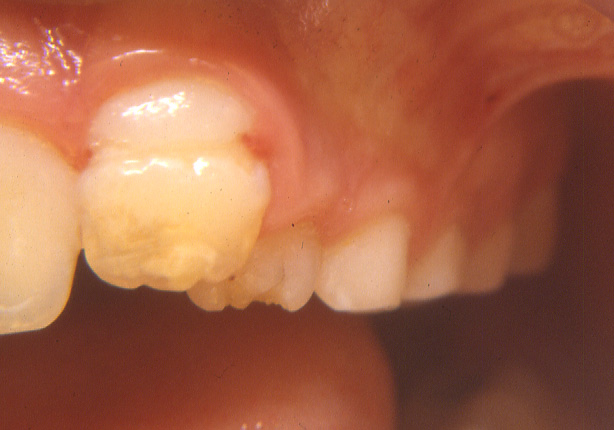

Danno sul permanente da trauma sul deciduo

Eruzione ectopica del permanente per trauma deciduo